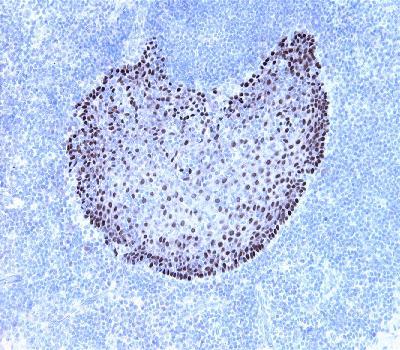

Figure-1: Human tonsil has been stained using P63a antibody (Clone: BS63). P63a is basal cell marker in squamous epithelial. p63 is a very useful marker for squamous, myoepithelial and urothelial neoplasm. Distinct nuclear staining. No unspesific staining. No cytoplasmic staining observed with optimized protocol X100